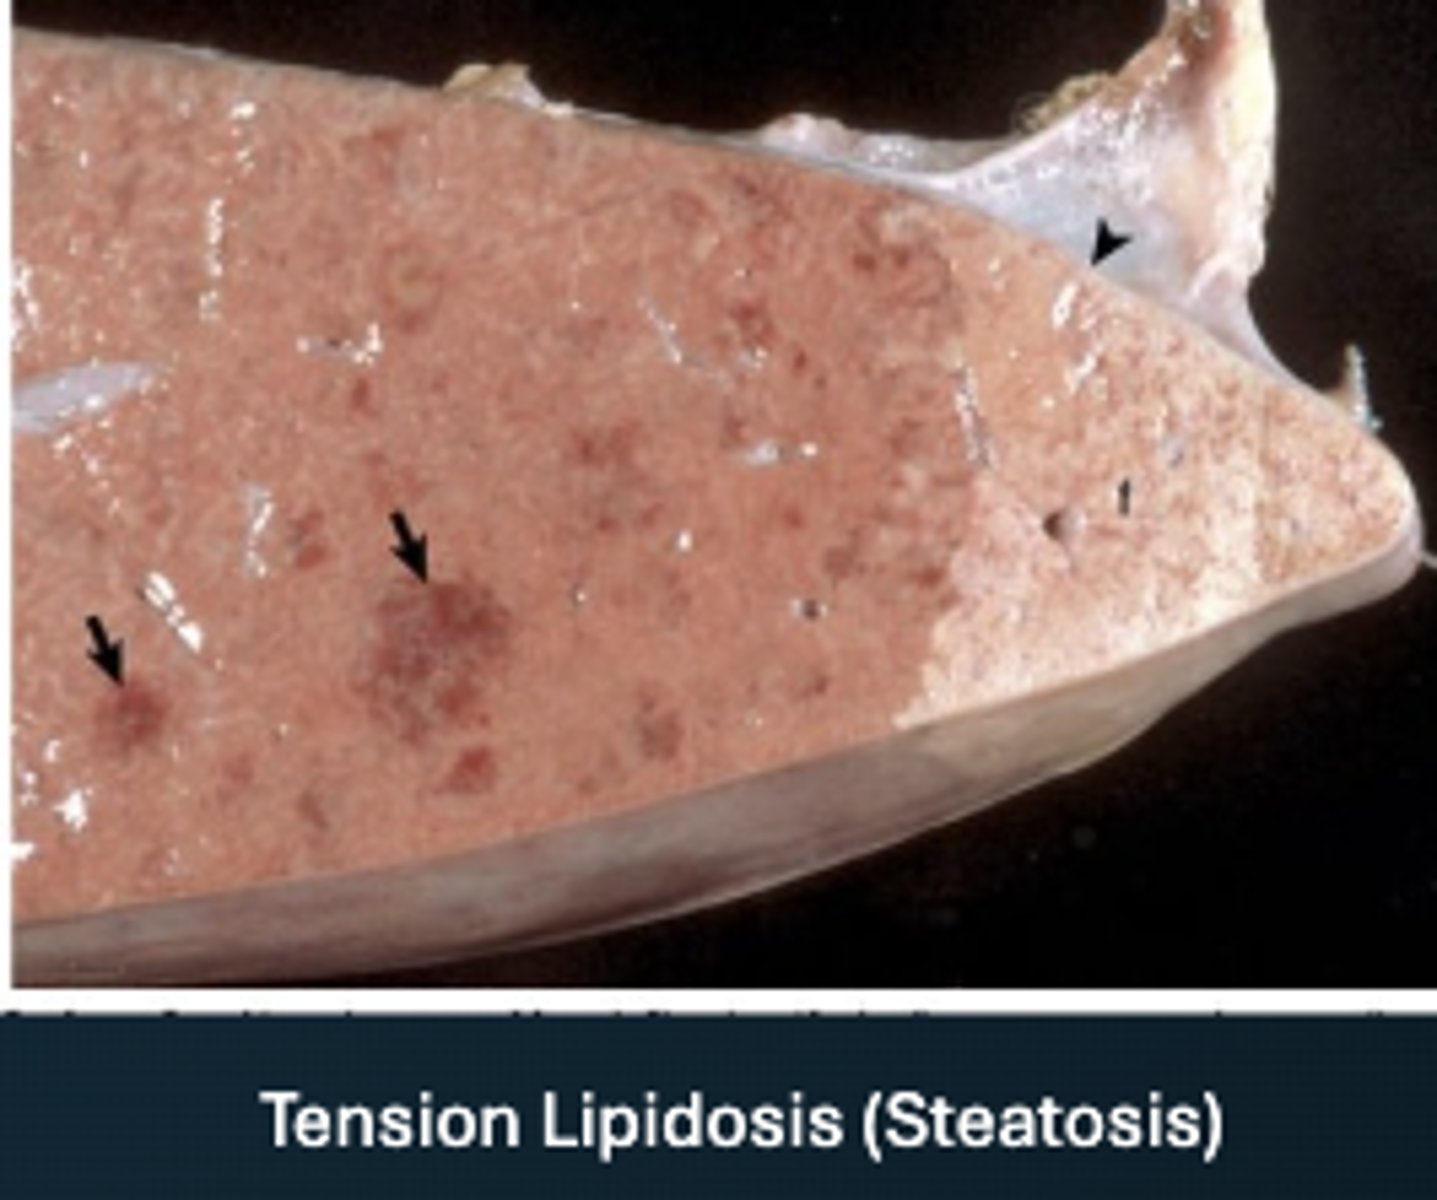

Tension Lipidosis

- doesn't have to effect the whole liver- can be regionally

-consequence of hypoxia

- where tension/ fat accumulation was= paler area

What has caused this gross appearance of this liver?

Tension lipidosis (steatosis)

What has caused this gross appearance of this liver?